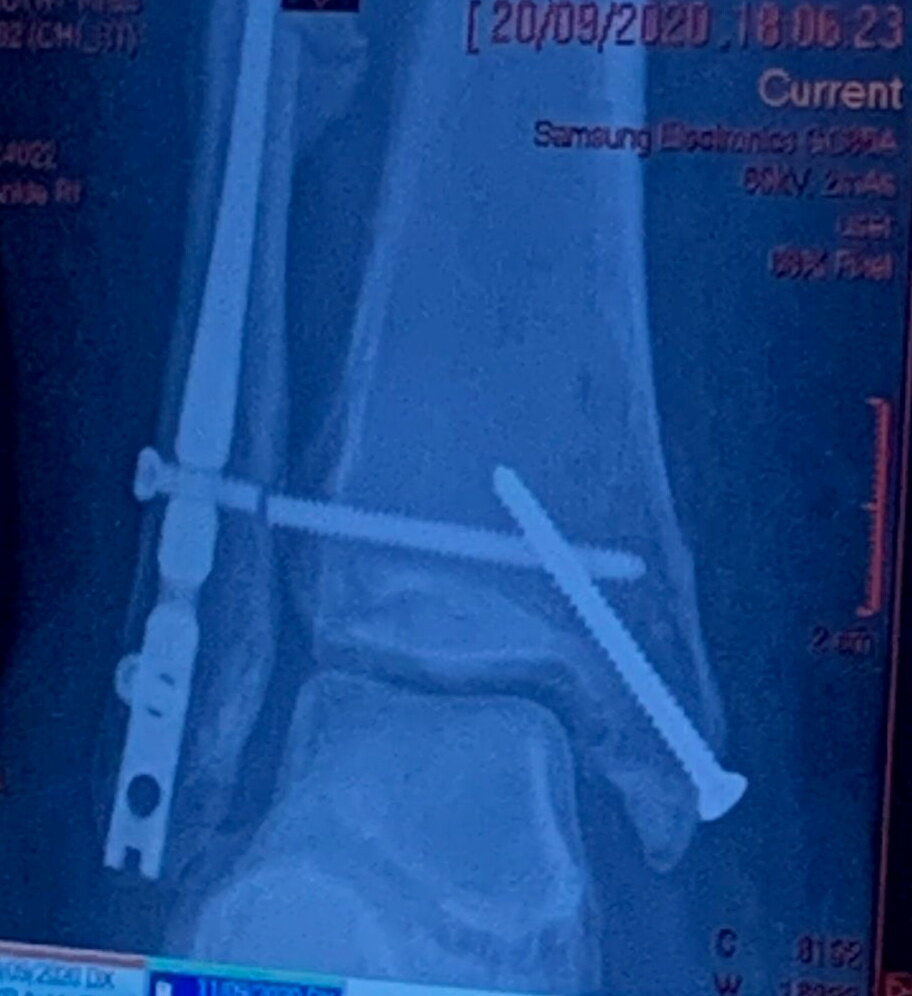

Шотландка получила разрыв связок и три перелома костей лодыжки. Хирурги скрепили лодыжку винтами и пластиной, однако они уверены, что в течение ближайших четырех лет у Эбби начнется артрит. "Рю повезло, она симпатичная", - признается Хэй. "Сначала я даже не могла смотреть на нее, но потом поняла, что она ни в чем не виновата".

Девушке была сделана операция по восстановлению ноги: врачи использовали две скобы и четыре винта, чтобы вернуть ее на место. После двух недель пребывания в больнице она провела 12 недель в гипсе и четыре месяца в ходунках. Но такая травма имеет долгосрочные последствия. "Моя лодыжка зарубцевалась… но теперь я плохо хожу, у меня постоянный отек - врачи сказали, что это не пройдет, и я больше не смогу носить туфли на каблуке".